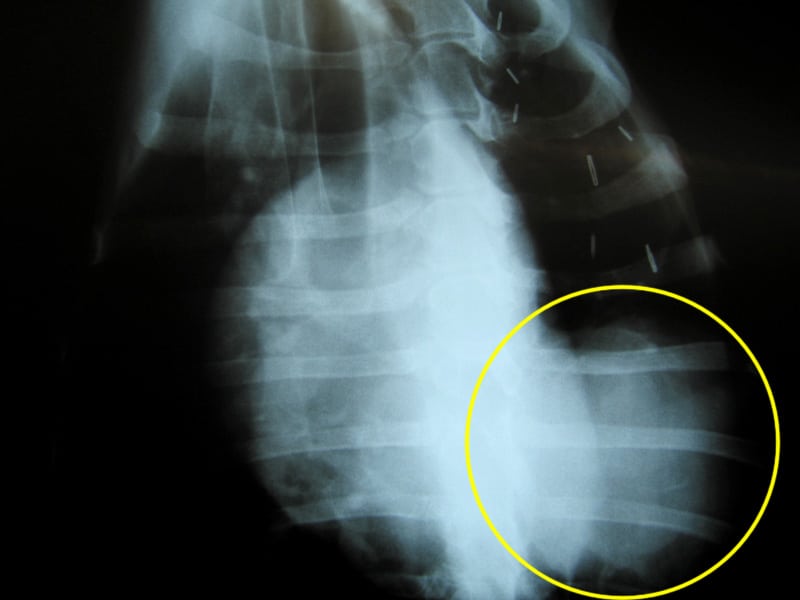

Tomorrow we’ll get the results from tests on blood and urine samples they took from me. But the films clearly indicate that I do indeed have a lump in my lung. More of a mass really, about the size of a softball from the looks of things. But as I have proven all along, I’m a special case.

osteosarcoma metastasis xrayUsually, osteosarcoma metastasis presents itself as multiple legions throughout the lungs. The doctor expected to see a “snowstorm” on the x-rays. And I could tell my people did too, deep down inside. Instead, I appear to have a single large growth, which may or may not be operable.

In fact, it may or may not have anything to do with my cancer at all. That’s probably not the case, but the doctor did mention the rare possibility that it could be totally unrelated. Perhaps he was just trying to keep our hopes up.

• Should they pay for the costly CT scan which that doctor would surely need to make any sort of accurate recommendations? (There may be other small lumps the x-ray didn’t show.)